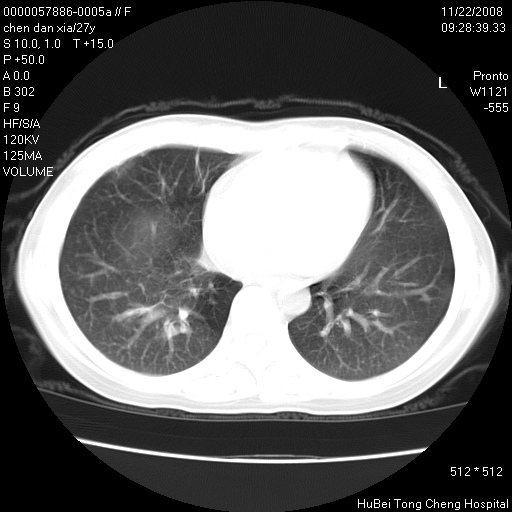

标题: CT16752:F,27Y。发热咳嗽20余天,伴盗汗。 [打印本页]

标题: CT16752:F,27Y。发热咳嗽20余天,伴盗汗。

考虑双肺粟粒性肺tb,右侧胸膜增厚.

气管前腔静脉后淋巴结肿大 右肺门纹理模糊

淋巴结核?

右下肺见片絮状影,两肺野内分布不均的小结节影,结核并肺内播散可能性大,建议结合实验室检查 .

右下肺纹理模糊;纵隔可见肿大淋巴节;右心缘旁结节,边缘光滑,纵隔窗病变范围较肺窗明显小,首先考虑右下肺结核,不排外淋巴瘤

双肺纹影普多,部分呈网状,支炎或淋巴管炎?

纵隔内淋结肿

局部胸膜增厚

下肺结节,结节内钙化,肺门纵隔淋巴肿大 结核可能性大

似有粟米状结节。考虑粟粒型肺结核?

1)考虑两肺感染性病变。2)纵隔淋巴结肿大。